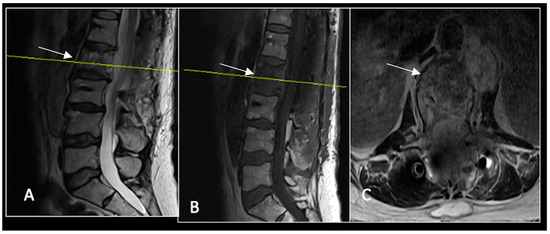

Figure 4.

MRI demonstrating a destructive lobular sacral mass (arrow) with invasion of the S1 vertebral body and complete compression of the cauda equina neural elements. The yellow line on the axial image represents the plane of the corresponding axial section. (A) T2W sagittal; (B) T1W sagittal; (C) T2W axial.